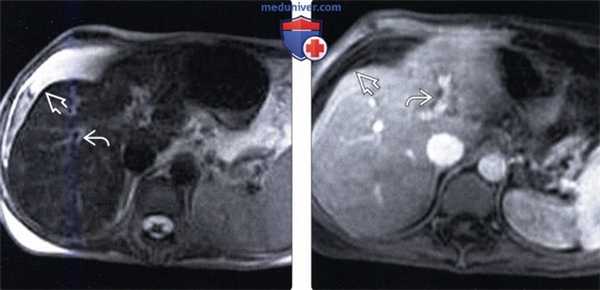

(Слева) На аксиальной Т2 ВИ МР томограмме у женщины 43 лет, страдающей веноокклюзионной болезнью, после курса химиотерапии по схеме FOLLOX по поводу рака червеобразного отростка, определяется асцит и перипортальный отек, которые сами по себе не являются специфическими находками. При исследовании биоптата печени были подтверждены застойные изменения в синусоидах и фиброз венул.

(Справа) На аксиальной Т1 ВИ МР томограмме с контрастным усилением у этой же пациентки определяется асцит и перипортальный отек.

2. МРТ признаки веноокклюзионной болезни печени:

• Асцит и перипортальный отек (в обоих случаях интенсивность сигнала на Т2 ВИ повышена)